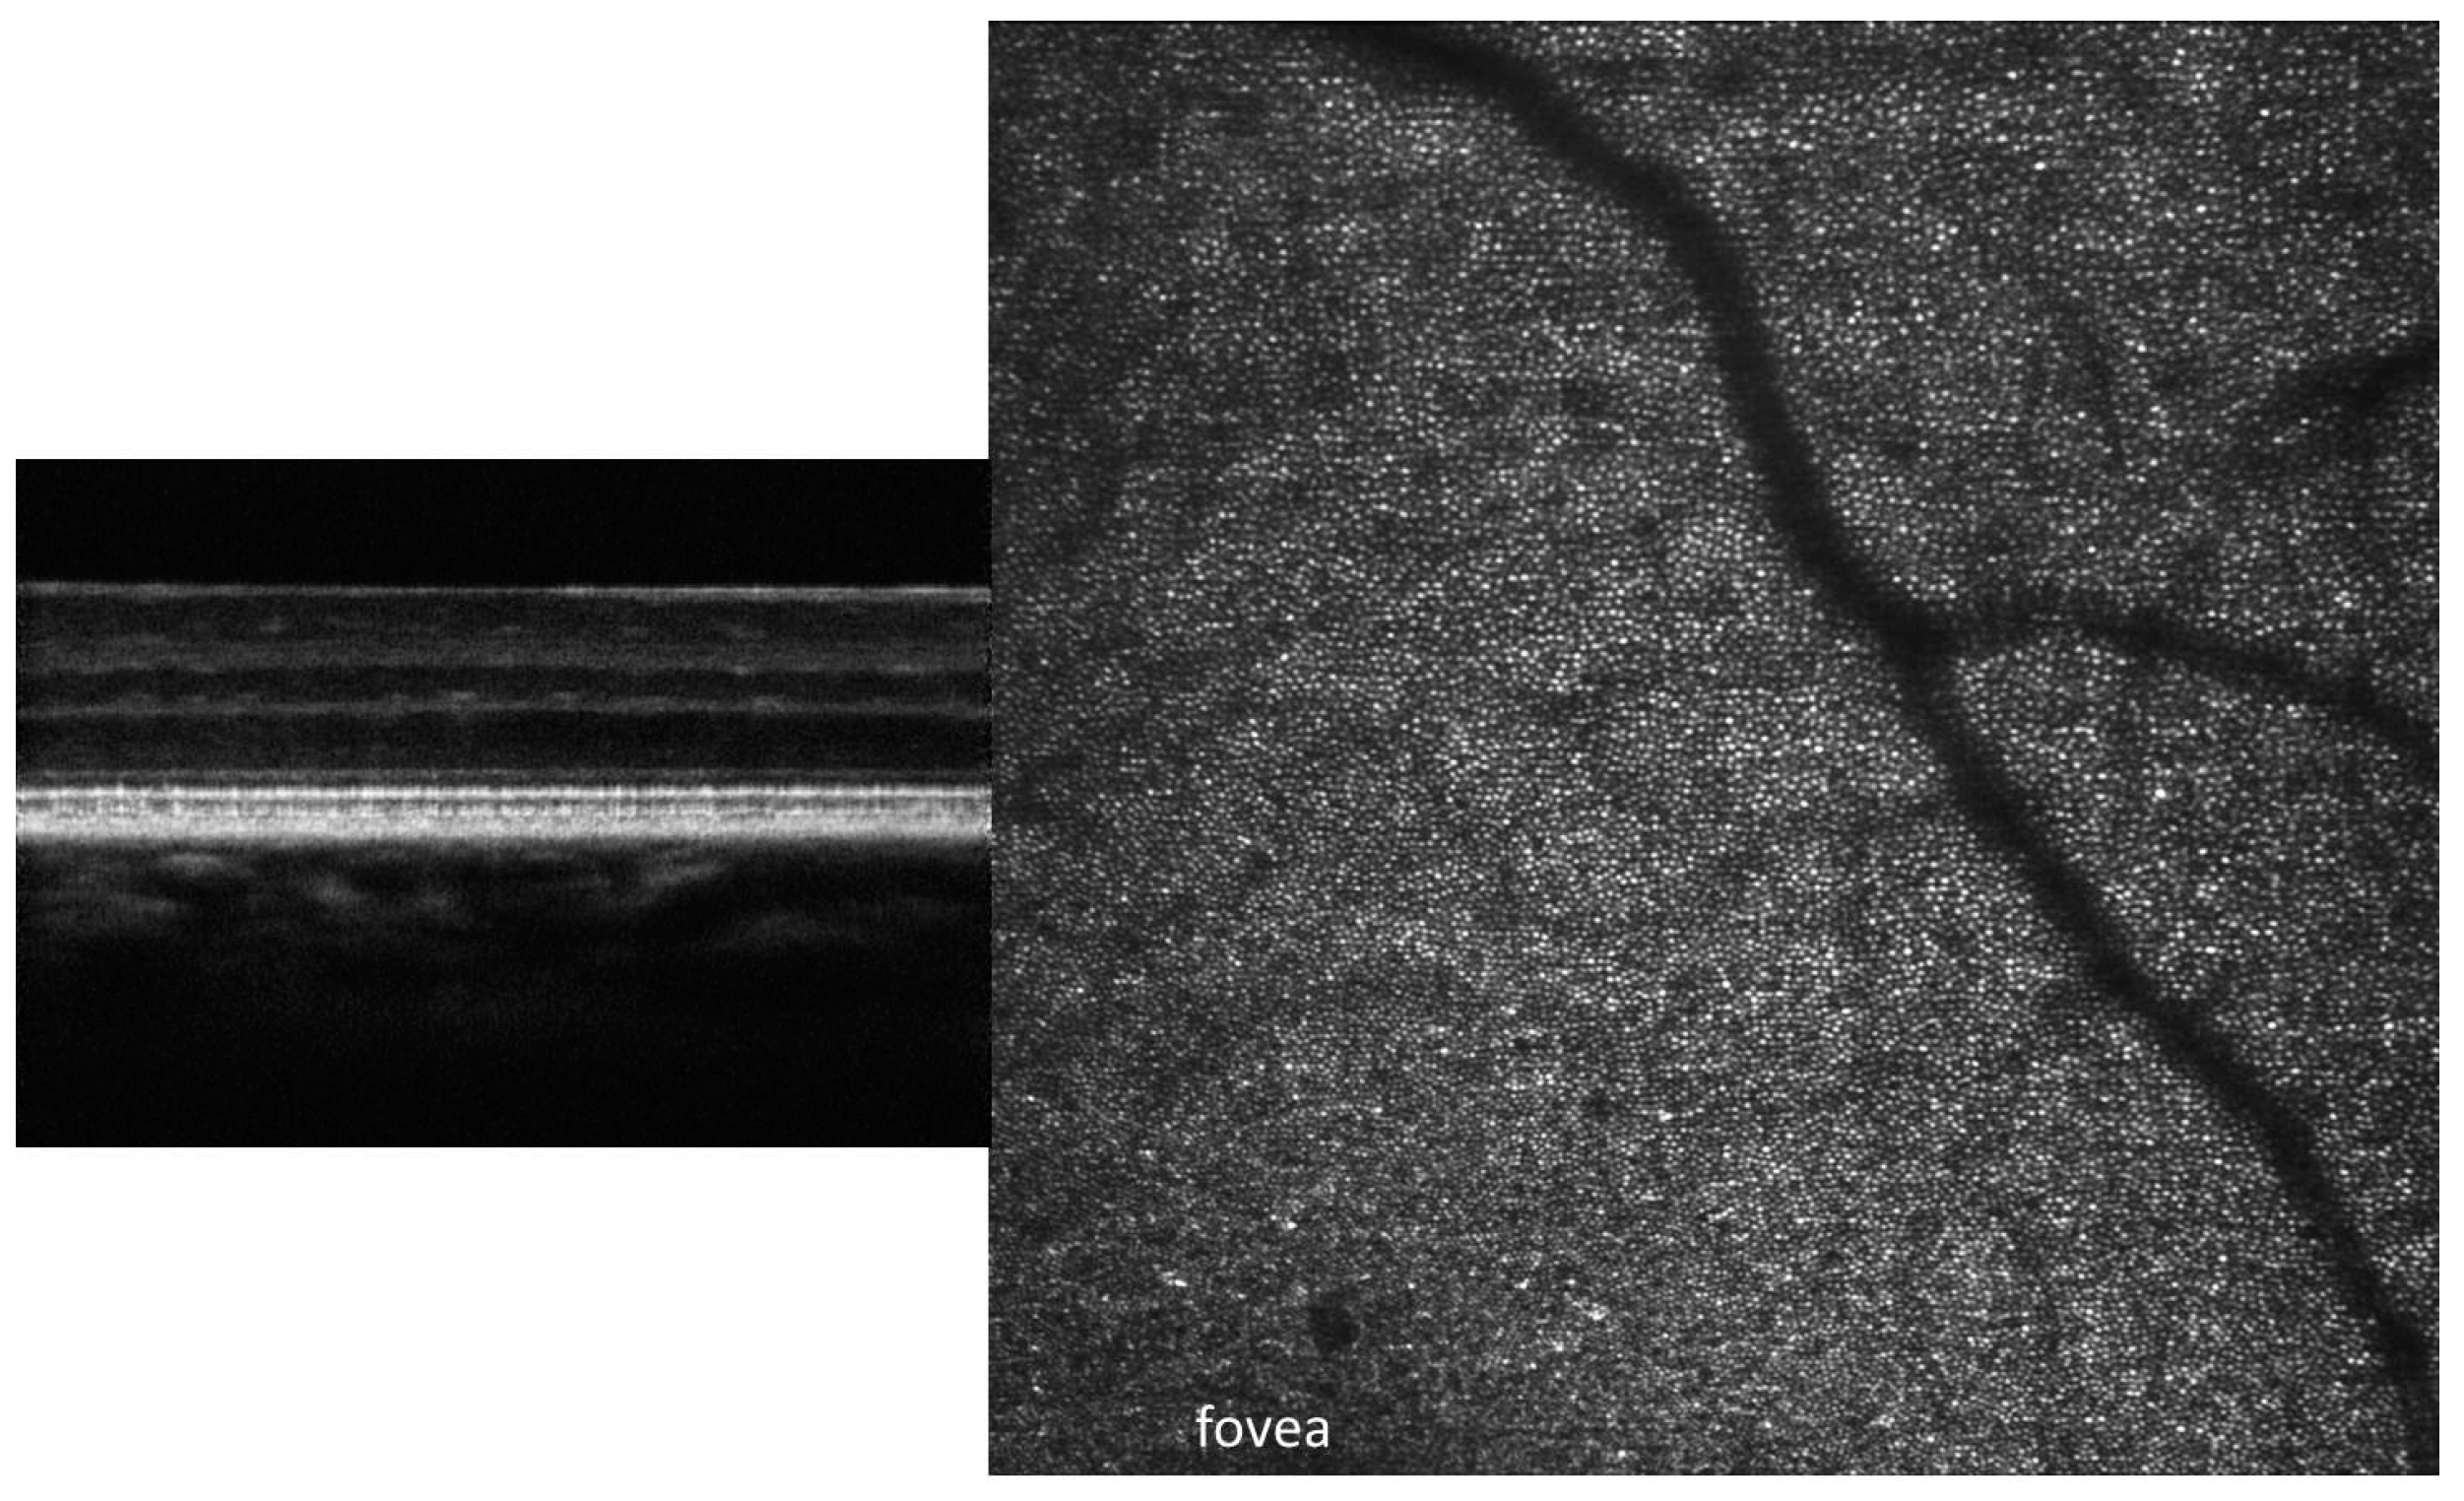

Recently, a non-rigid registration method for aligning a stack of confocal images has been presented [65]. The images used to demonstrate that method were obtained with the BCH MAORI. At the time, the imager had only the confocal AO-SLO channel. An example of the cone mosaic from a healthy volunteer is shown in Figure 8, with several magnified regions shown in Figure 9 for better visualization. The fovea is in the center (white *), and the image demonstrates that the cones are well resolved to within 0.3°–0.4° of the fovea.

An upgraded version of the BCH MAORI included two offsets simultaneously recorded with the confocal channel. Figure 10 shows an example of the confocal, SPL, SD, and STD images obtained from a healthy volunteer. The BCH MAORI was later upgraded again to include all four offsets and the confocal in a configuration that was included in all PSI retinal imaging platforms.

Figure 8 shows the confocal images of the cone mosaic near the fovea, and Figure 9 shows the four magnified patches (from the yellow squares locations in Figure 8). The density of the cones varies across the eye. The largest density is needed at the center of the fovea for the best visual acuity. However, the eye geometry limits the resolution of the AO-SLO/OCT imaging system, and foveal cones are very difficult to resolve.

Figure 10 shows the four images obtained with different contrast mechanisms derived from the simultaneously acquired confocal and offset channels: confocal, SPL, SD, and STD. They illustrate the complementarity of these images. Nerve fiber bundles can be clearly seen in the SLO image but not in the others. The capillary map is nicely visible in the STD image, hard to see in SPL and SD, and completely hidden in the SLO. SPL and SD reveal details of the vessel walls that are not seen in the other images. Similarly, Figure 11 also illustrates this complementarity. Both figures were obtained from healthy volunteers. However, Figure 11 shows several microstructures, as highlighted by the circles in the SPL and PG images, which have no correspondence in the STD and, therefore, no flow associated with them. They could be harmless, or they may raise flags as potential locations for disease initiation, especially the ones near the vessel wall.

Figure 8. Examples of the cone mosaic in a healthy eye in confocal imaging mode. Image size—1.5° (~450 µm) each panel. The white * indicates the center of the fovea.

Figure 9. Magnified patches from regions delineated in Figure 8 by yellow squares. Image size—0.25° (~70 µm) each patch.

Figure 10. Examples of the SLO, split, SD, and STD images highlighting the complementarity of different contrast mechanisms given by confocal, offset, and motion contrast modes. Image size—1.4° (~420 µm).